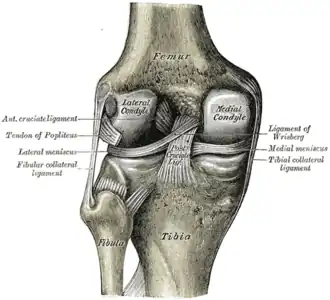

O joelho é uma articulação do corpo humano e de outros mamíferos. Formada pela extremidade distal do fêmur, pela extremidade proximal da tíbia (e pela patela (rótula).

O joelho ainda possui ligamentos que estabilizam a articulação, auxiliados pelos meniscos (interno ou medial e externo ou lateral), que estabilizam o joelho, e amortecem os impactos sobre as cartilagens.

Os ligamentos são os estabilizadores primários para a translação anterior e posterior, angulação vara e valga, e para a rotação interna e externa da articulação do joelho. O ligamento cruzado anterior (LCA) é a restrição predominante ao deslocamento tibial anterior, pois aceita 75% da força em extensão completa e um adicional de 10% (até 90.º) de flexão do joelho. Com esses dados fica evidente que o LCA é o mais exigido no dia a dia de uma pessoa saudável, que pratica esporte por lazer ou profissão.

Ligamentos

| Nome | Cápsula | Origem | Inserção | Descrição |

| ligamento cruzado anterior (LCA) | dentro | côndilo lateral do fêmur | área intercondilar anterior | O papel do LCA é prevenir o deslizamento anterior excessivo da tíbia em relação ao fêmur |

| ligamento cruzado posterior (LCP) | dentro | côndilo medial do fêmur | área intercondilar posterior | A lesão deste ligamento é incomum, mas pode ocorrer resultando de uma força de tração traumática do ligamento. Este ligamento previne o deslizamento posterior excessivo da tíbia em relação ao fêmur. |

| ligamento colateral medial ou ligamento colateral tibial (LCM) | fora | epicôndilo medial do fêmur | condilo tibial medial | O Ligamento Colateral Medial protege a parte medial do joelho de ser aberto por uma força aplicada nas laterais do joelho (joelho valgo). |

| ligamento colateral lateral ou ligamento colateral fibular (LCL) | fora | epicôndilo lateral do fêmur | cabeça da fíbula | o Ligamento Colateral Lateral protege as laterais do joelho de uma força dobrante interior (joelho varo). |